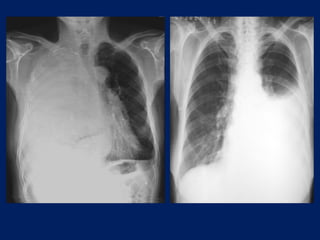

EXAMENES COMPLEMENTARIOS

• Radiografía de tórax.

Se aprecia un aumento de la transparencia del lado

correspondiente al neumotórax, con el pulmón retraído

hacia el hilio, dando una forma de muñón característico.